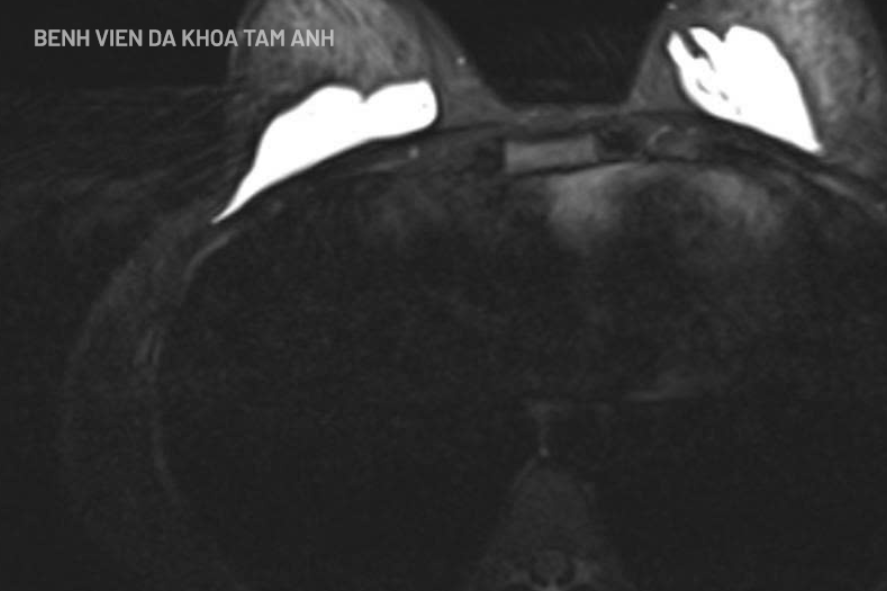

Thăm khám ban đầu, chị Lê không có dấu hiệu viêm cấp song có nhiều sẩn cục dưới da tuyến vú và vùng mông. Khi chụp MRI ngực ghi nhận hình ảnh chất làm đầy khu trú phía sau nhu mô tuyến vú và trước cơ ngực lớn. Siêu âm vùng mông cũng phát hiện các ổ dịch rải rác không đồng nhất dưới da.

Hình ảnh chất làm đầy khu trú phía sau nhu mô tuyến vú chị Lê. (Ảnh: BVCC)